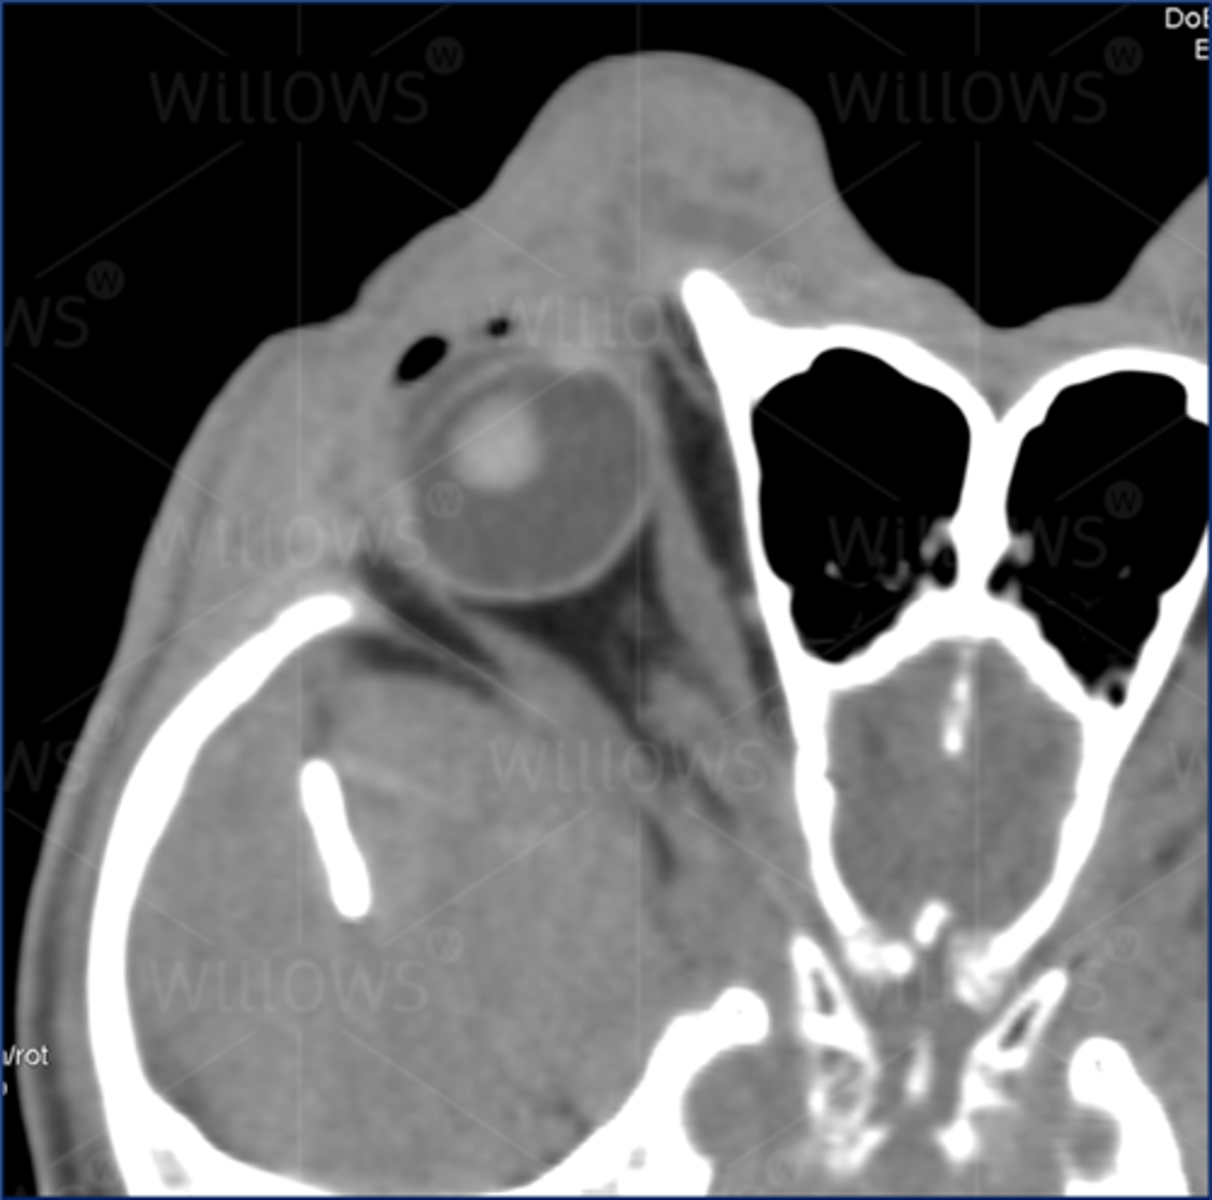

Weimaraner with tumour behind right eye